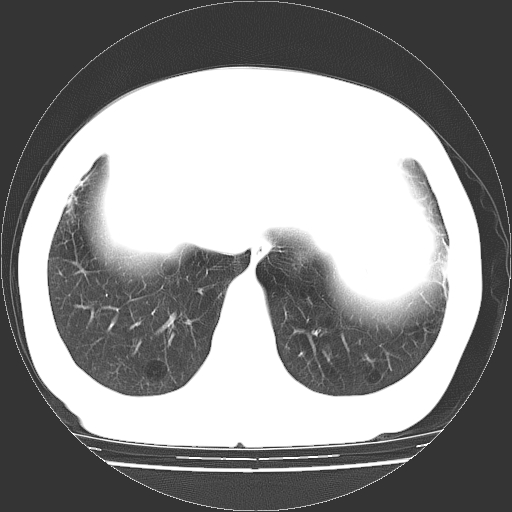

女,70岁,咳嗽、胸闷半个月。纵隔窗未见异常,未上传。

慢支炎、肺气肿征,双肺多发肺大泡

小叶中心型肺气肿并多个肺大泡形成。

小叶中心性肺气肿及间隔旁肺气肿.(多与吸烟有关)

慢性支气管炎合并小叶中心性肺气肿及间隔旁肺气肿.(多与吸烟有关)。

慢性支气管炎合并小叶中心性肺气肿,多发性肺大泡

1.小叶中心型肺气肿。

2.左肺下舌段感染性病变。

肺大疱的壁甚薄,由肺泡的扁平上皮细胞组成,也可能仅为纤维性膜。可与多种肺气肿并存,常见于间隔旁侧或细叶旁肺气肿,可伴有碳末沉着,如煤矿工人尘肺,或不伴有碳末沉着,如瘢痕组织肺气肿。根据病理形态将肺大疱分为三种类型。

ⅰ型:狭颈肺大疱。突出于肺表面,并有一狭带与肺相连。因为支气管瘢痕组织形成的活瓣性阻塞,肺大疱体积增大系由于肺泡侧支通气和气体滞留。ⅰ型肺大疱壁薄,常由胸膜和结缔组织形成,多发生于中叶或舌叶,也常见于肺上叶,可能由于该部位胸腔负压大,常规胸片即可发现肺大疱的存在。

ⅱ型:宽基底部表浅肺大疱。位于肺表层,在脏层胸膜与气肿性肺组织之间。肺大疱腔内可见结缔组织间隔,但它不构成肺大疱的壁,可见于肺的任何部位。

ⅲ型:宽基底部深位肺大疱。结构与ⅱ型相似,但部位较深,周围均为气肿性肺组织,肺大疱可伸展至肺门,可见于任何肺叶。

当肺大疱体积增大时,周围肺组织受压迫并引起肺脏移位。受压肺组织在x线胸片上,表现为肺大疱周围密度增高阴影。以上三型均见于慢性支气管炎。小叶中心型肺气肿不并发肺大疱。下叶肺大疱常见于有并发症的煤矿工人尘肺和融合性矽肺。